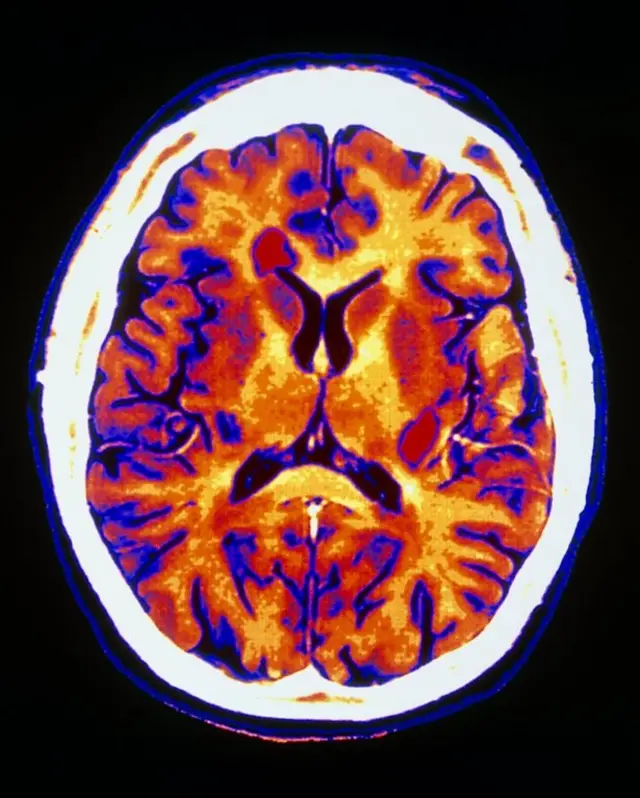

در بدن هم همین طور است، روی رشته عصبی را لایهای محافظ به نام میلین میپوشاند. در بیماری ام اس، سیستم ایمنی به دلایل ناشناخته، ترکیبی از عوامل محیطی و ژنتیکی، به این غلاف میلین حمله کرده و آن را تخریب میکند.

این تخریب علاوه بر اینکه خود عصب را در معرض آسیب قرار میدهد هدایت جریان الکتریکی در عصب را هم مختل میکند، انگار سیم برقی که عایقش کنده شده دچار اتصالی شود.

این باعث میشود اعصاب نخاعی و مغزی که دیگر لایه محافظ ندارند بتدریج دچار تحلیل و تخریب شوند که نتیجه آن معلولیت و ناتوانیهای مختلف است.